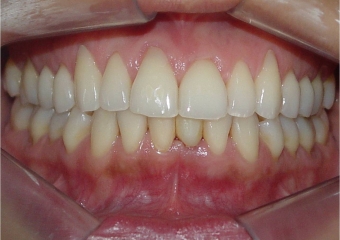

Imagens do dente provisório fixo imediato, no implante Cone Morse Facility